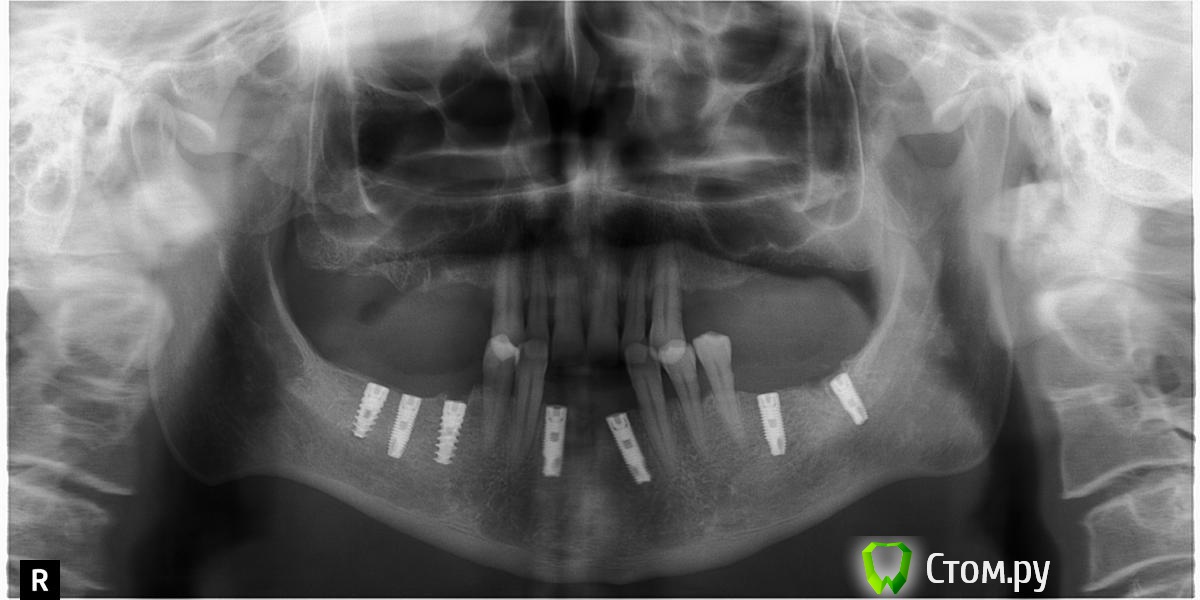

ILGAMSA Опубликовано 3 февраля, 2014 Автор Поделиться Опубликовано 3 февраля, 2014 задался этим вопросом около 6 мес назад делал подобные имплантации для сравнения.в абсолютно одинаковых условиях при заглублении на 0.5 мм Spi зарастает , у atid убыль ровно 1 мм.а я взаимосвязи с этим не вижу.http://s019.radikal.ru/i642/1402/83/88c28ba7b835.jpg 1 Ссылка на комментарий

RINAT05 Опубликовано 3 февраля, 2014 Поделиться Опубликовано 3 февраля, 2014 Возможно я слишком всматриваюсь но в этой ситуации наблюдал тоже самое только в области атида . Ссылка на комментарий

RINAT05 Опубликовано 3 февраля, 2014 Поделиться Опубликовано 3 февраля, 2014 Возможно я слишком всматриваюсь но в этой ситуации наблюдал тоже самое только в области атида .В области дистальных имплантатов справа хорошо видно образование кортикальной пластинки над spi и отсутствие над atid Ссылка на комментарий

kriokov Опубликовано 3 февраля, 2014 Поделиться Опубликовано 3 февраля, 2014 В области дистальных имплантатов справа хорошо видно образование кортикальной пластинки над spi и отсутствие над atidНе фактскорее там сохраненная язычная кортикальная на панораме проецируетсяощутимой разницы по снимку не вижу, одинаково нормально с костью в 4 сегменте Ссылка на комментарий

RINAT05 Опубликовано 3 февраля, 2014 Поделиться Опубликовано 3 февраля, 2014 (изменено) Не фактскорее там сохраненная язычная кортикальная на панораме проецируетсяощутимой разницы по снимку не вижу, одинаково нормально с костью в 4 сегментефакт, когда открыл имплантаты в Spi видно только шестиграник в заглушке остальное под костью, в 3 м сегменте заглушки все вровень с костью , открыты. Изменено 3 февраля, 2014 пользователем RINAT05 Ссылка на комментарий